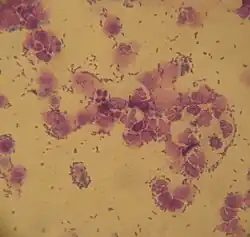

Urinalysis is essential in chronic kidney disease in cats. Damage to as little as two thirds of the nephrons results in a reduced ability to concentrate urine and the specific weight falls below 1030 N-m−3. Protein loss via the kidney is detected by an increase in the protein/creatinine ratio in the urine (UPC), as 24-hour collection samples are impractical in cats. The UPC is a good marker for the early detection of CNE, as it reveals renal dysfunction even before the creatinine in the blood rises.[8] The urine sediment can also show effusions from the renal tubules (cylinder), and in chronic bacterial renal pelvic inflammation bacteria or pus can also be detected. The detection of small amounts of albumin (< 300 mg/l, "microalbuminuria") is very sensitive, but not very specific for chronic kidney disease.[25]